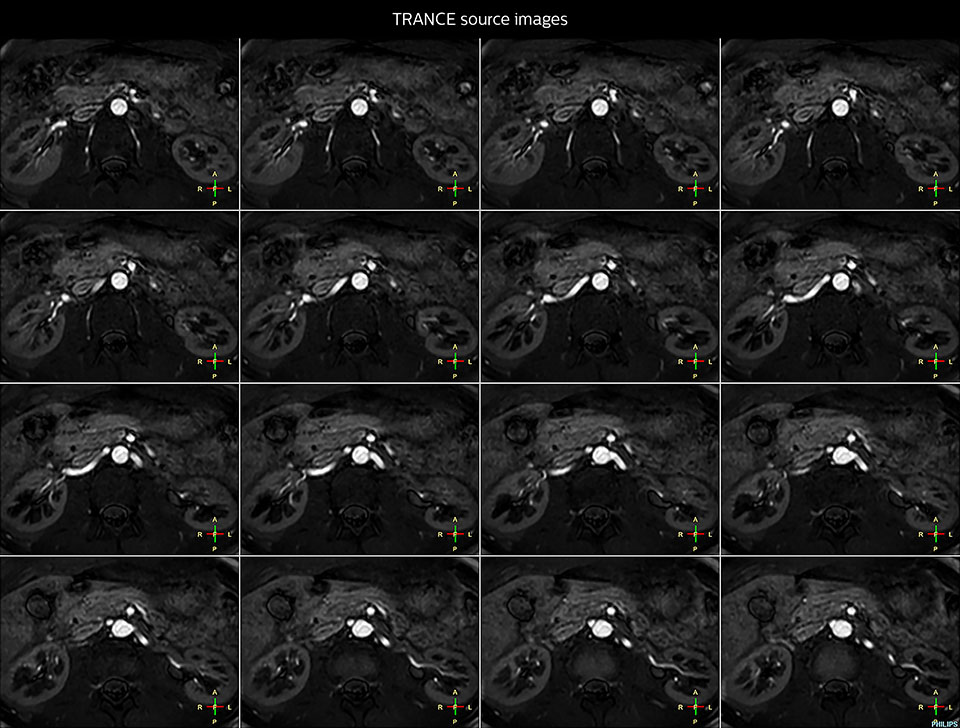

Positioning and operation: smooth and simple Once the scanner was in place, Mrs. Schiffer and her staff received tailored training in line with their clinical and workflow requirements and objectives. “I have been impressed from the start. Installation and set-up were smooth and simple. Within three days, our technologists were confidently using the new system,” recalls Mrs. Schiffer. Since installing Prodiva 1.5T, she and her team have noticed a number of enhancements to their daily work. The scanner’s simple Breeze workflow supports easy patient positioning with fewer positioning steps, rapid set-up and changeover times. Ultra-light anterior coils, short cables and small connectors are making technologists’ lives easier. Senior MRI technologist Sandra Maass says: “Speaking for myself and my colleagues, we all very much enjoy using Prodiva – and we benefit from its many workflow advantages every day.” And Mrs. Schiffer adds, “The flexible, lightweight coils fit really well to the patient’s body shape, and the connectors are superb: connecting and disconnecting requires just little effort.” “The shoulder coil is a great example of easy positioning with Prodiva,” says Mrs. Maass “Other shoulder coils can be quite rigid, so that patients with pain, or bigger stronger shoulders, or a somewhat abnormal shoulder or spine anatomy cannot be positioned well in the coil, which often leads to loss of image quality. However, the Prodiva shoulder coil is very flexible and has large coverage, which makes good positioning easier and that contributes to the superb image quality and high SNR that we get in our shoulder exams.” High quality of images impresses From a clinical perspective, too, Mrs. Schiffer is very impressed with Prodiva 1.5T. In her practice around 50% of scans are neurological, 40% musculoskeletal and the rest made up of vascular, abdominal and miscellaneous cases. The radiology team is receiving good results across anatomies, which their referring physicians are confirming to them. “Prodiva’s high image quality and advanced features, including diffusion-weighted imaging in many organs, improve our diagnostic confidence and help decision-making,” says Mrs. Schiffer. “Prodiva has been an excellent investment and is definitely the right choice for us.” “The quality of the contrast-free MR angiography keeps impressing us,” says Mrs. Schiffer. “In addition to not having to inject contrast agent, these images are amazing, for instance of the carotids. Also our exams of shoulders and hands are really exceptional. Images of the hands, for example, cover the fingertips and include the full wrist as well, all with high signal-to-noise ratio.”

Imaging the renal arteries without contrast agent on Prodiva 1.5T.